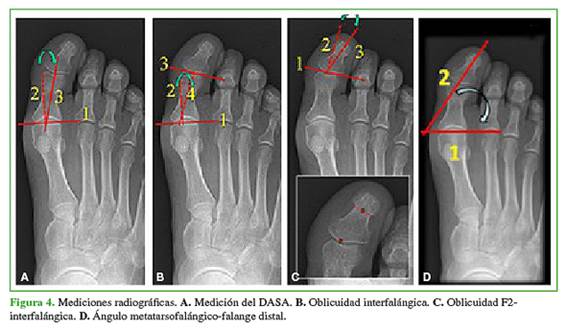

Las mediciones se realizaron en radiografías de incidencia anteroposterior del pie, con el paciente parado sobre sus dos pies, soportando su peso corporal. Se registraron y analizaron los siguientes ángulos antes de la cirugía y en el posoperatorio a largo plazo (Figura 4):

1. DASA, trazando una tangente a la carilla articular proximal de la falange. De allí, se traza la perpendicular a la tangente, y se mide el ángulo que forma esta perpendicular con la línea del eje diafisario de la falange proximal. Los valores normales son de 0° a 8°.

2. La oblicuidad de la articulación interfalángica (OIF)12 que se mide tomando el ángulo donde se cruzan las perpendiculares a las líneas tangentes de ambas carillas articulares (proximal y distal de la primera falange).

3. La oblicuidad F2-interfalángico (F2-IF)12 que se mide por el ángulo formado entre el eje de la falange distal y la perpendicular a la tangente a los cóndilos de la falange proximal.

4. El ángulo falange distal-articulación MTF (F2-MTF): se toma la resultante del entrecruzamiento de la tangente a la base de la primera falange y el eje longitudinal de la falange distal.